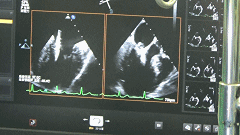

完全在超声引导下完成二尖瓣夹的定位、瓣叶抓取和二尖瓣夹的释放

此方法完全在超声引导下完成,无需传统的体外循环、心脏停跳,更大程度的避免了手术创伤,创伤小、恢复快,由于其入路距离二尖瓣较近、操控性更加灵活,在处理1区、3区瓣叶关闭不全等复杂二尖瓣关闭不全时相对其它微创方法更有优势、治疗效果也更加确切。本例患者当日即脱离呼吸机并由重症监护室转回普通病房,此项技术的开展未来可为东北地区众多二尖瓣反流患者提供治疗新策略,带来新希望!